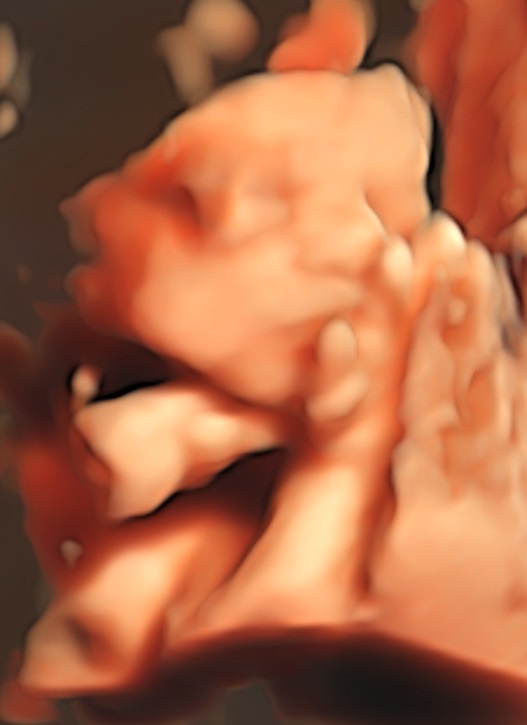

Mooi man, hoeveel weken is ze nu?

Precies 26 weken, gaat snel

Ja ze lijkt op jou